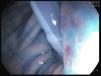

Reportamos el caso de un varón de 44 años de edad, residente de un asilo, bajo alimentación enteral mediante gastrostomía endoscópica percutánea (PEG), desde que sufrió una embolia 2 años antes. De manera accidental se extrajo su sonda de alimentación. Para prevenir el cierre de la gastrostomía, le fue colocado de inmediato una sonda de Foley. Después de varias horas, presentó vómito. Al día siguiente, se llevó a cabo una endoscopia después de haber administrado azul de metileno mediante el catéter. Reveló que la sonda de Foley había atravesado el antro gástrico (fig. 1) con el globo migrando al duodeno (fig. 2) causando obstruccion parcial (fig. 3).

El catéter fue retirado, se introdujo una sonda de PEG, 20F de Bard®, resolviendo así la obstrucción. En casos de extracción accidental de sondas de PEG, con el objeto de evitar que la gastrostomía se cierre, con frecuencia se utilizan sondas de Foley, ya que son fáciles de pasar mediante la gastrostomía y se encuentran disponibles en la mayoría de las instituciones de salud. Sin embargo, no cuentan con un borde externo y la peristalsis podría arrastrar el globo al duodeno originando obstrucción pilórica. En lugar de proceder con la inserción de una sonda de Foley, se debe referir rápidamente a los pacientes a algún centro hospitalario durante las primeras 24h, para poder colocar una sonda de PEG adecuada. Si la remisión temprana resulta imposible, el balón de Foley deberá ser inflado de forma mínima, para prevenir la migración al duodeno y la obstrucción pilórica (figs. 1-3).